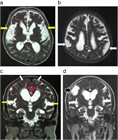

1. 頭部画像所見では、脳室拡大所見とともに

1. 不均衡に拡⼤したクモ膜下腔(脳溝)所見であるDESH(Disproportionately Enlarged Subarachnoid Space)所見

1. 拡大したシルビウス裂所見、高位円蓋部脳溝の狭小化所見、急峻な脳梁角所見などに注目する。

1. 画像診断上、DESH所見、脳梁角の急峻化所見が、iNPHの診断、手術効果予測に有用である。